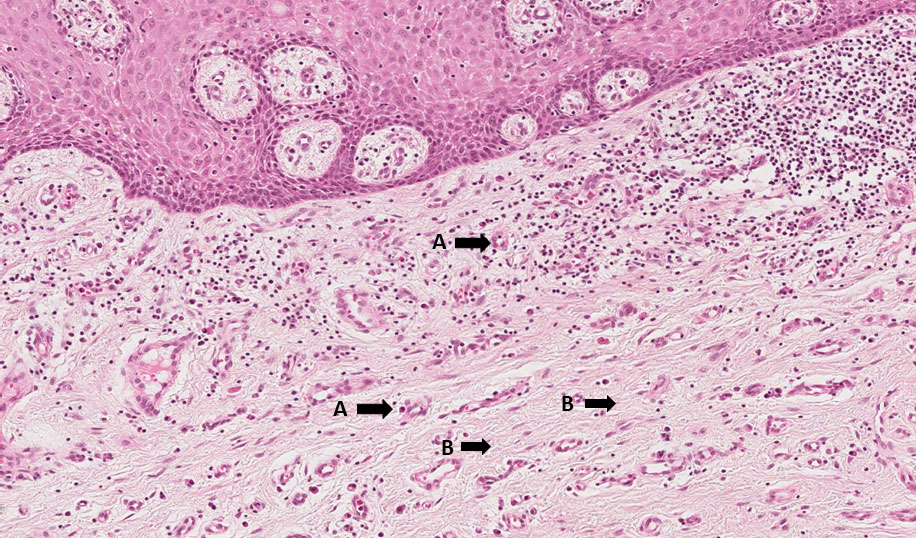

Fragmento de mucosa revestido por tecido epitelial estratificado pavimentoso ceratinizado. Subjacente a ele, vemos o tecido conjuntivo com intensa fibroplasia, angiogênese e células inflamatórias crônicas (linfócitos, plasmócitos e macrófagos).

Angiogênese (setas A), fibroplasia (setas B), infiltrado de linfócitos (asterisco amarelo) e plasmócitos (asterisco vermelho) → Tecido de granulação.